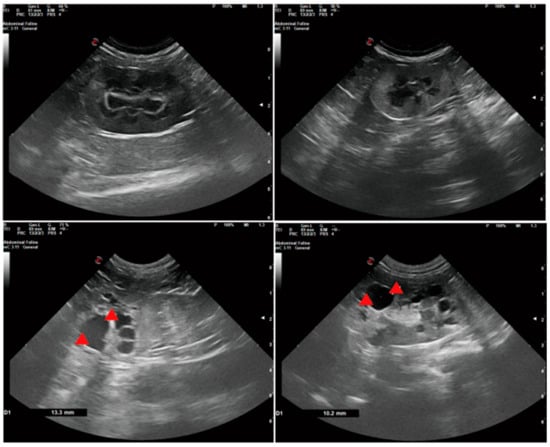

| Imaging studies | Ultrasound, CT scanning, MRI | Ultrasound |